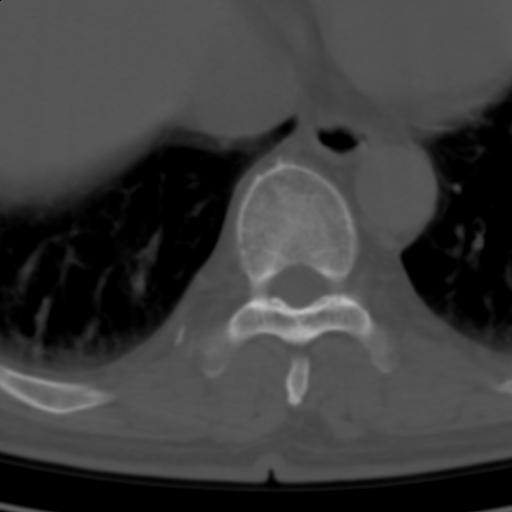

标题: CT25189:胸椎ct,请会诊!

既往食管癌,现行ct检查!

中上段食道癌,椎体轻度退变。

支持中上段食道癌,椎体轻度退变,必要时做ect。